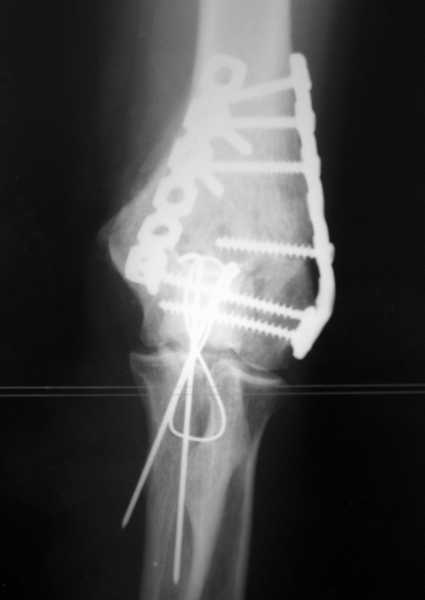

У пациентки 42 лет после операции остеосинтеза чрезмыщелкового перелома плеча, выполненной в нашей клинике 2 месяца назад, на контрольных R-граммах имеется гетеротопический оссификат по передней поверхности плеча. Оперирована по методике АО, после операции максимально рано начала заниматся ЛФК. В настоящее время основная жалоба пациентки на ограничение сгибания в локтевом суставе. Клинически объем движений: сгибание 90 градусов, разгибание 170 градусов, ротационные движения в полном объеме. Привожу снимки сразу после операции и через 2 месяца. (На рентгенограммах после операции в мягких тканях по передней поверхности плеча имеется небольшой костный фрагмент, но его ширина во фронтальной плоскости не более 1 мм., обнаружен был по снимкам после операции. Интраоперационно основные крупные фрагменты отрепонировались хорошо, объем движений был сгибание до 75 градусов, разгибание 175 град.) Пациентка неудовлетворена объемом сгибания, хотя была предупреждена о высокой вероятности ограничения движений. Профилактика гетеротопической оссификации (прием индометацина) не проводилась, т.к. имелась язвенная болезнь, да и эффект от его приема считаю сомнительным. Вопросы: 1.Стоит ли вмешиваться и пытаться удалить экзостоз? Если да,то в какие сроки и каким доступом лучше идти? 2. Оставить все как есть? 3. Не поможет ли ударно-волновая терапия либо какая-то другая методика? Буду благодарен за все ответы и оценки своей работы. С таким осложнением столкнулся впервые.

В данном случае лучше ни чего не трогать до года, произойдет консолидация, затем при удалении металла можно будет сделать артропластику с удаление оссификата и освободить передний отдел, а возможно к тому времени и задний. Пациентка должна поддерживать имеющийся объем движений.

Доступ обычно наружно-боковой без опаски, если не удается все достать, то внутренний боковой с выделением локтевого нерва(безопасней и спокойней). ФЗТ на локтевом суставе обычно без эффекта.